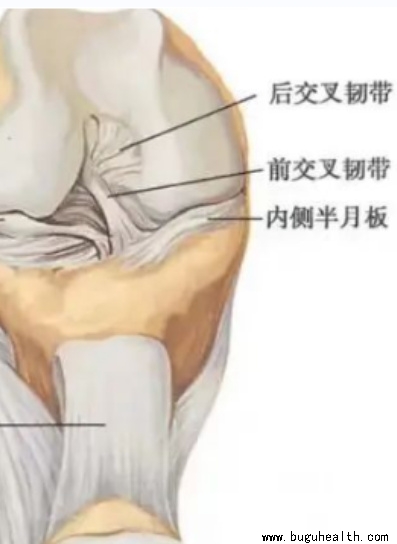

- ���°���ϥ�ؽ����ֹǺɹǼ�϶�ڵ���ά��״������֯����۳ʡ�C���ͣ��ʳ�Ϊ���°塣λ��ϥ�ؽ��ڲ�Ľ����ڲ���°壬���ơ�C���ͣ����Ľ��������°壬���ơ�O���͡������ڲ���°���ؽ����ܱ����ӽ��ܣ���Բ�����°��Ǵ����N������϶������Դ��°��ڹؽ��ڰ���ϥ�ؽ�һ���˶�����������.....

- ���°���ϥ�ؽ������һ��������֯�����֪����ϥ�ؽ������ŹɹǺ��ֹǣ����ǹɹ��¶�������Բ���ֹ��϶�������ƽ̨���������ֱ������Ļ����Ӵ����������㣬����������ѹǿ��ܴ����ǻ�ܿ챻ĥ�𣬲������ϵ��ȶ��Ի�ܲ�����εİ��°��������֮���ý�飬�ùɹǺ��ֹǵĽӴ����������ϱ�ý��ܶ��ȶ�����.....